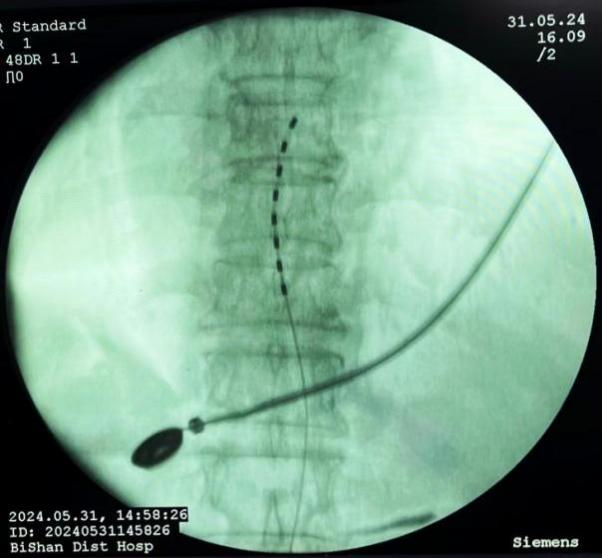

脊髓電刺激植入術(shù):將電極植入脊柱附近硬膜外腔,通過電流刺激脊髓,阻斷疼痛信號傳至大腦,有效治療慢性頑固性神經(jīng)痛。

脊髓電刺激植入術(shù)